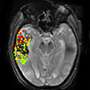

![]() | New imaging method may predict risk of post-treatment brain bleeding after strokeIn a study of stroke patients, investigators confirmed through MRI brain scans that there was an association between the extent of disruption to the brain's protective blood-brain barrier and the severity of bleeding following invasive stroke therapy. The results of the National Institutes of Health-funded study were published in Neurology. |